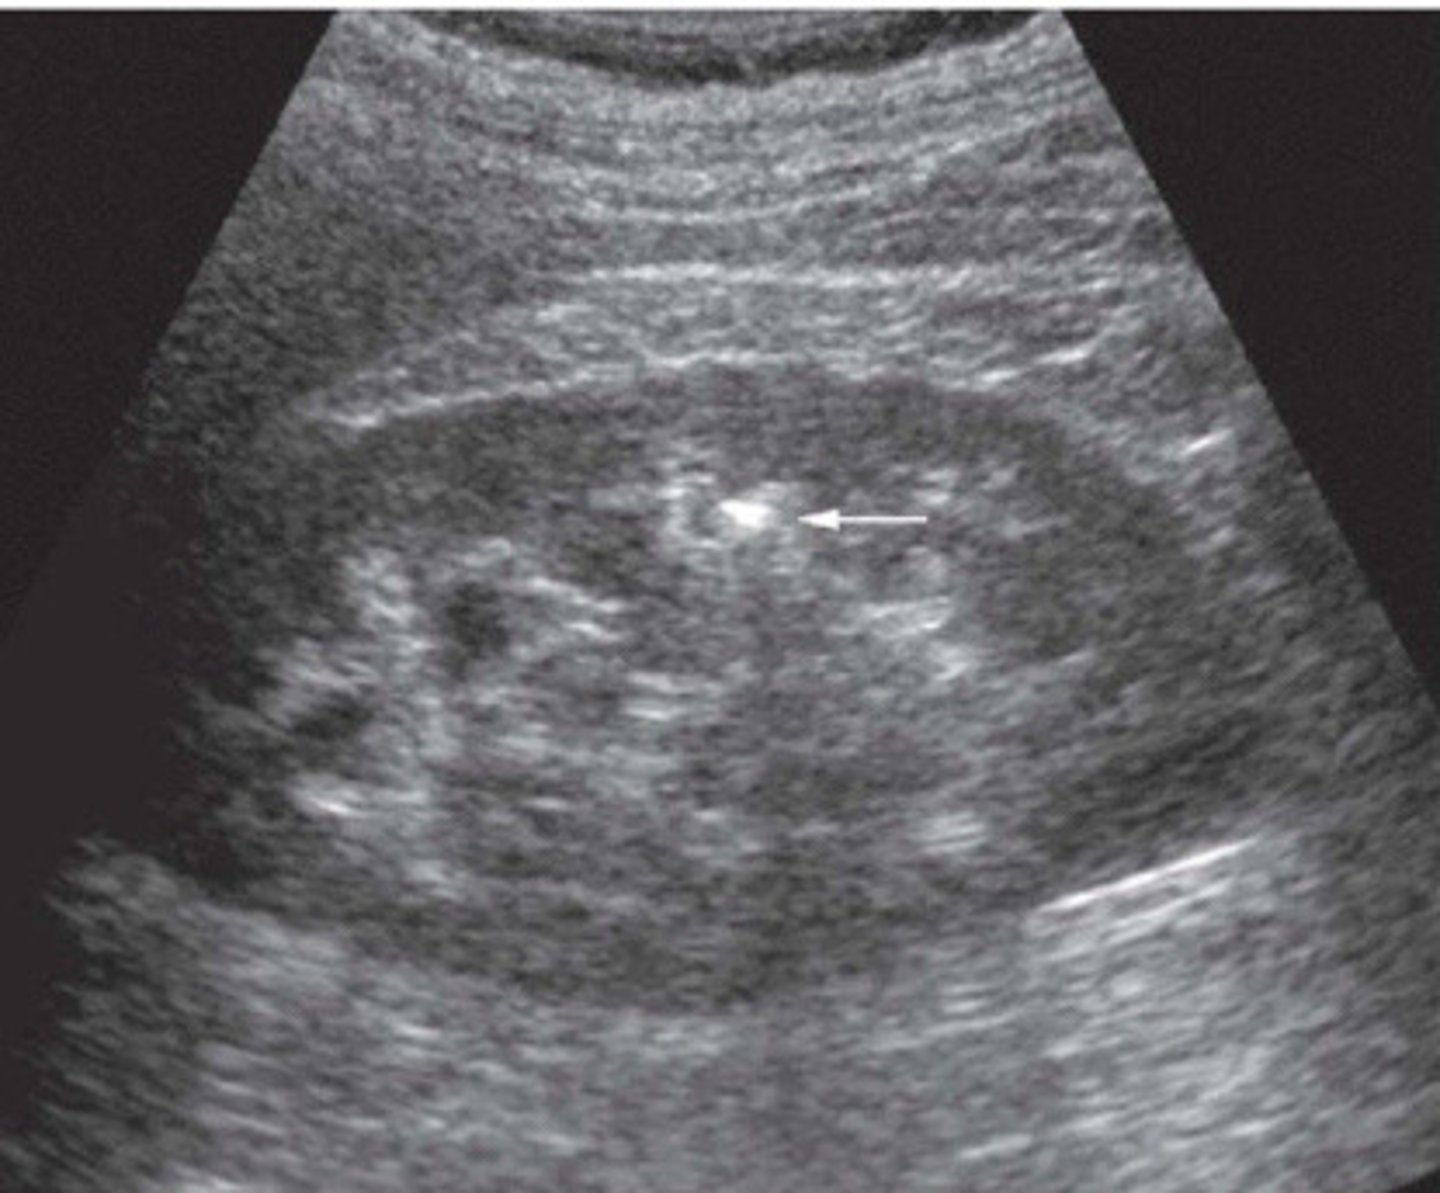

Stone now identified with the twinkle artifact

What does this image show

Colour reverberation

What is the twinkling artifact

Colour or power Doppler

What mode do you have to use in order to be able to see the twinkling artifact